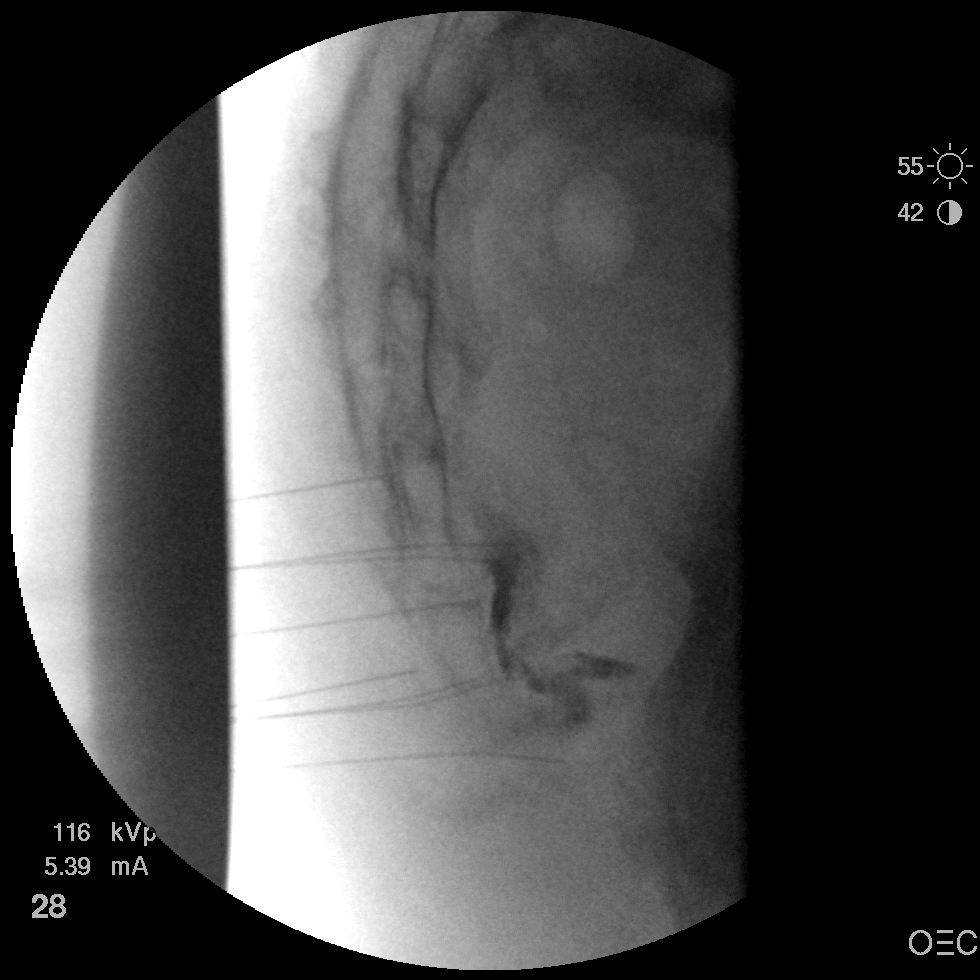

I have a patient with several months of coccyx pain. Worse with sitting, TTP over coccyx. Otherwise normal exam. No trauma, but she has an anteriorly displaced coccyx. Failed NSAIDs and no one around me does good pelvic floor PT. I scheduled her for ganglion impar injection, but her insurance won't pay for it. They wouldn't even let me to a peer-to-peer... they just straight up said they won't cover it. Any other treatment options? I don't want to send her to a surgeon. Thanks.